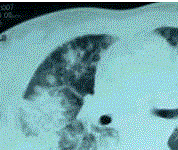

问题 患者女,23岁。间断发热伴皮疹1年半,诊断红斑狼疮。长期间断应用糖皮质激素治疗。近20 d来高热(T 39℃)伴咳嗽咳痰, CT(附图)示双肺满布圆形密度增高阴影,大小不等,密度不均匀,上、中肺野分布较多,双侧少量胸腔积液。血常规:WBC 2.52×10/L, N 0.62, Hb 92 g/L;ESR 40 mm/h;痰真菌培养:烟曲霉3次阳性;支气管镜检查右下叶、左舌段见黄色黏液性血性分泌物,毛刷找到霉菌孢子。 肺部病变可能诊断为

选项 A.红斑狼疮的肺部并发症 B.合并大叶性肺炎 C.合并 ARDS D.合并肺真菌感染 E.肺部转移瘤 F.肺结核

答案 D